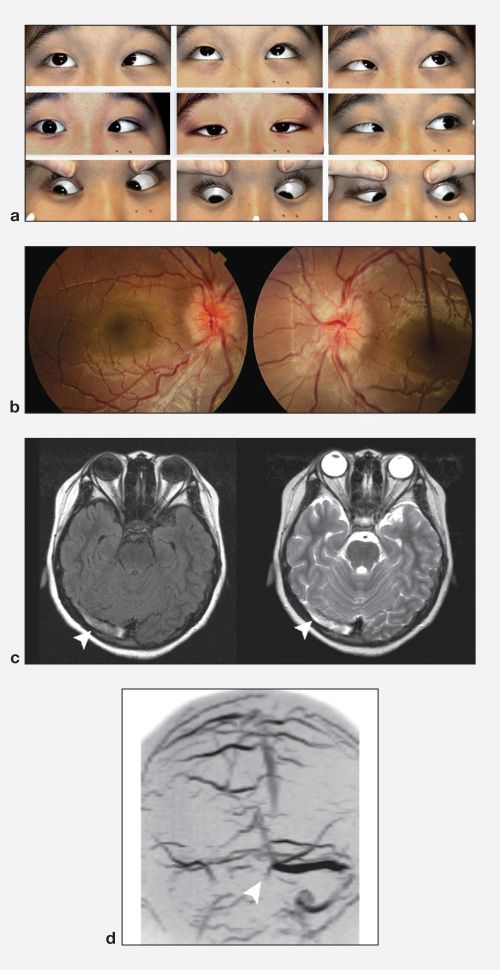

- Visual problems: Visual problems are a common presenting sign/symptom in CVST according to the ISCVST. Visual loss (13.2%), papilledema (28.3%), and diplopia (13.5%) were all noted. Migraine-like visual phenomena (colored photopsia, dark spots, and visual blurring associated with vertical wavy lines), have also been reported. Papilledema is often seen with CVST and there is a direct association of papilledema with elevated ICP. However, in eyes in previous papilledema that have resulted in optic atrophy, the absence of papilledema cannot be used as a marker for raised ICP. Other facial or craniofacial pains may be present as well. If

The clinical presentation of a CVST can be variable and the diagnosis should be suspected in patients with new onset focal neurological deficits, signs of increased ICP, seizures, or mental status changes. A complete ocular exam including dilated fundus examination, visual field examination, and optic nerve photographs are recommended in patients with CVST.

Diagnostic procedures

MRI/MRV: MRI T2 weighted imaging with MRV is the most sensitive test for identifying CVST . The appearance on MRI is dependent on the age of the thrombus. In the acute setting (days 1-5), the thrombus is typically hypointense on T2 and isointense on T1 weighte MRI. The subacute thrombosis (days 6-15) is usually strongly hyperintense on both T1 and T2 weighted images. After 3 weeks, the signal becomes irregular and either flow was restored or a persistent thrombus was seen. [19]

CT/CTV: Non-contrast head CT is usually the first test ordered with new onset neurological deficits. This test is not very specific for CVST and is abnormal in only approximately 30% of cases. In the roughly 30% of cases where CT reveals a CVST, an empty delta sign may be seen represented as a dense triangle in the posterior portion of the superior sagittal sinus. In areas where MRI/MRV are not as readily available CTV may be added to CT to aid in the suspected diagnosis. [20]